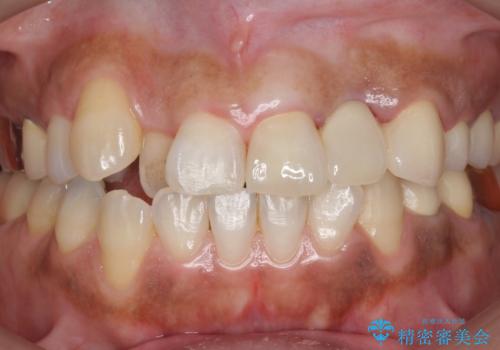

- 左上2番目の歯がグラグラするので診て欲しいといらっしゃった方の症例です。

左上2番目の歯は歯根が破折してため抜歯し、左上123のブリッジによる欠損補綴を行いました。

左上4、5番目の歯は根尖病変を認めたため再根管治療を行い、オールセラミッククラウンによる補綴を行いました。

今回用いたオールセラミッククラウンは、ジルコニアフレームという白い素材の上にセラミックを盛っているため審美性が非常に高いのが特徴です。

またジルコニアは人工ダイヤモンドの材料にも使われているほど高い強度を持っており、そのためオールセラミッククラウンは審美性だけでなく、奥歯やブリッジの補綴も可能とするクラウンです。